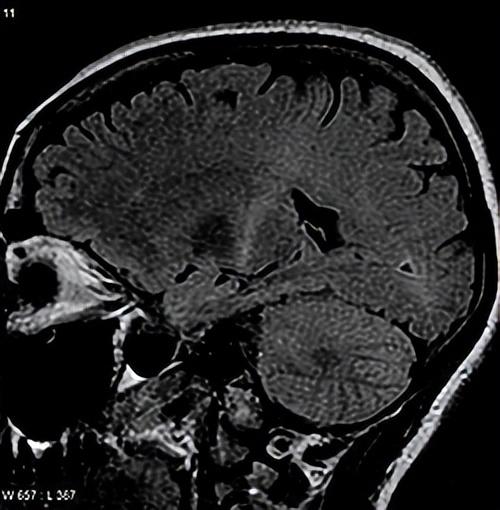

如果真的可以脑机接口,事情会很不一样。什么是脑机接口?就是让大脑直接连上机器,用大脑去控制外部设备,或者让外部设备把信息传回大脑。蔡磊说的非侵入式脑机接口指的是通过戴头盔、脑电帽、头箍等方式进行连接,这种方法用得最早最安全,但信号比侵入式、半侵入式弱。

但是理想很丰满,现实很骨感。脑机接口想做到像科幻电影那样随心所欲控制身体、恢复正常功能,估计还需要很长时间。非侵入式的脑机接口因为隔着头骨,信号弱,还容易受头发、环境甚至心情影响。侵入式虽然信号强一点,但需要开颅手术,风险大。而且,每个人的脑信号都不一样,要花很久训练,而目前区分不同想法的准确率还不高,特别是表达复杂意思更困难,速度也远达不到正常说话和打字的水平。